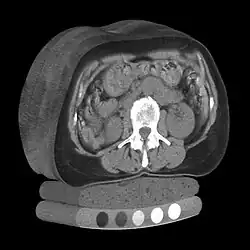

In scientific visualization and computer graphics, volume rendering is a set of techniques used to display a 2D projection of a 3D discretely sampled data set, typically a 3D scalar field.

A typical 3D data set is a group of 2D slice images acquired by a CT, MRI, or MicroCT scanner. Usually these are acquired in a regular pattern (e.g., one slice for each millimeter of depth) and usually have a regular number of image pixels in a regular pattern. This is an example of a regular volumetric grid, with each volume element, or voxel represented by a single value that is obtained by sampling the immediate area surrounding the voxel.